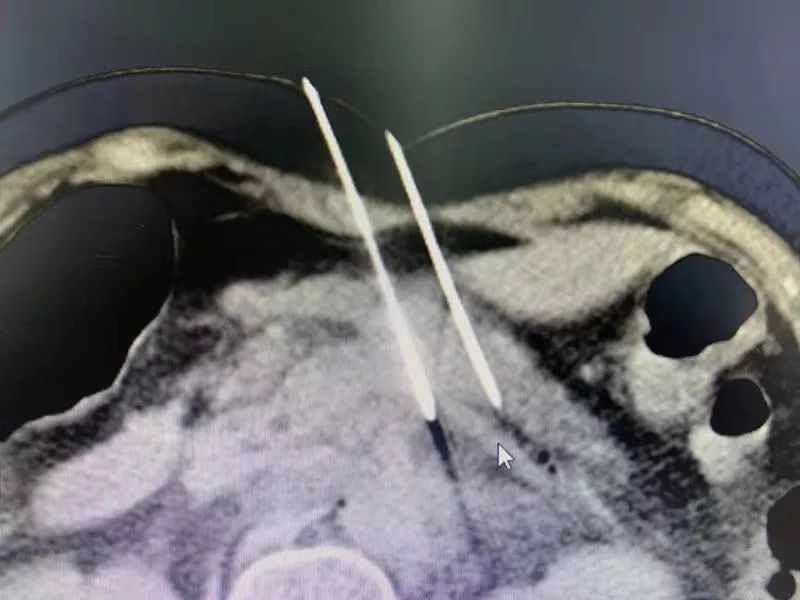

纳米刀

这还是要从纳米刀的原理讲起,纳米刀又称为不可逆性电穿孔,它可以把肿瘤消融掉,而不伤害正常的纤维架构,所以让组织能够再生,它把癌细胞电死以后,癌细胞周围的架构可以完整保留,所以癌细胞死掉之后,正常组织可以保住。这是纳米刀最大的优势。

手术前